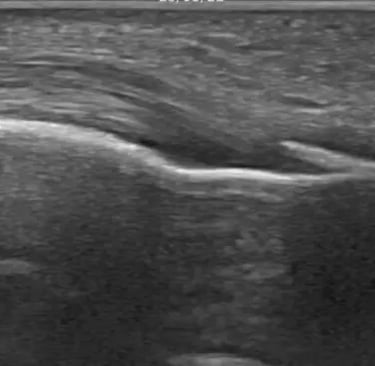

Además de la exploración física y los test diagnósticos, la ecografía nos ayuda a: localizar el depósito, valorar el estado del tendón y de los tejidos alrededor, elegir el tratamiento más adecuado y controlar la evolución.

La EPI se realiza con guía ecográfica para aplicar un estímulo local muy preciso en el tendón.